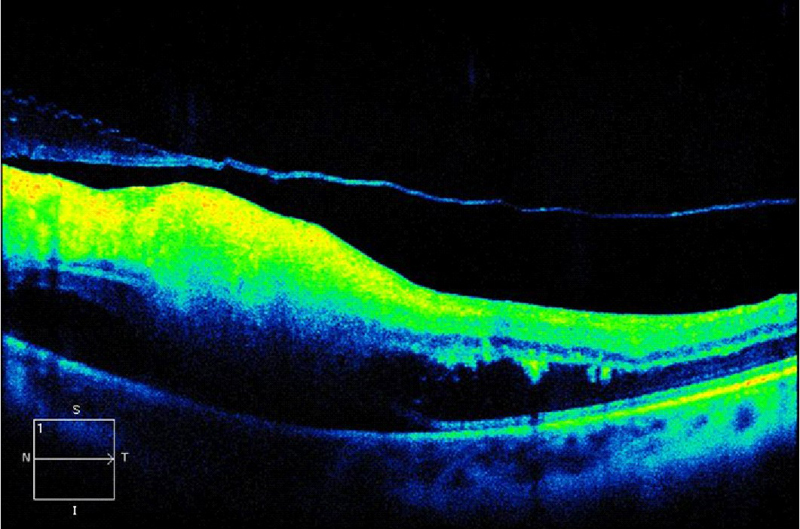

Figura 3. Paciente que presenta en su ojo izquierdo edema macular quístico y desprendimiento de retina seroso subfoveal asociado a uveítis posterior por Brucella. Mediante la OCT se monitoriza la respuesta al tratamiento con un implante intravítreo de Ozurdex, observándose como disminuye el grosor retiniano a medida que se reabsorbe el fluido y se normaliza el perfil foveal tras el tratamiento.

3-5. Tanto el EMQ como el EMD pueden asociarse a DRS (

Tabla 2 y

Figura 4,

Figura 5,

Figura 6 y

Figura 7).

Figura 4. Edema macular quístico (EMQ).

Figura 5. Edema macular difuso (EMD).

Figura 6. Desprendimiento de retina seroso (DRS) en una paciente con uveítis asociada a enfermedad de Behçet.

Figura 7. Desprendimiento de retina seroso subfoveal asociado a edema macular quístico en una paciente con coroidopatía tipo Birdshot.